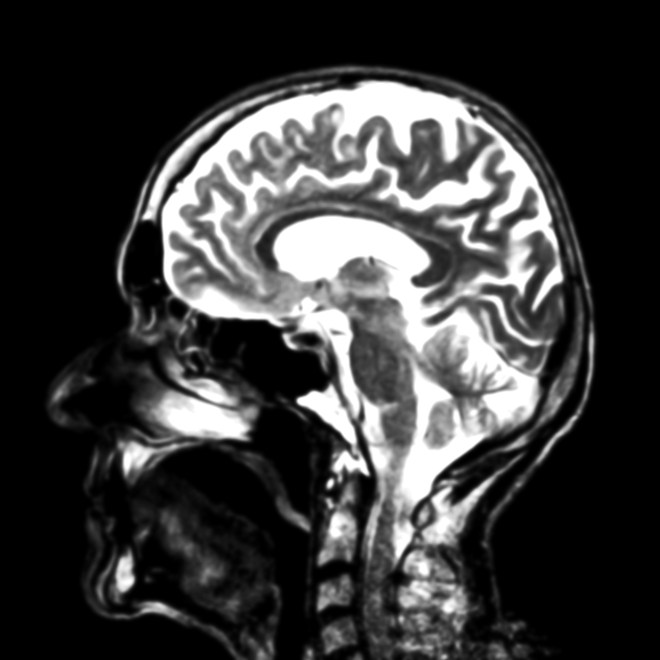

When I look at an MRI scan, I also see patterns:

and my brain does something similar… In essence, my brain is simplifying the structure, highlighting some differences and reducing others. It’s filtering the image down to something like this:

BUT the gradations of grey-scale on a sofa don’t mean the same thing as in an MRI scan of the brain. The original image actually contains far more gradations of grey than I can probably perceive…

But using Photoshop or another image processing program you can get the computer to mark them, and use false coloring to exaggerate the differences. Doing that to the original image produces this:

It’s not necessarily true that this rendering contains more functional information than the simpler one, but I’d bet it does. How meaningful are these new substructures? That’s for the experts to decide, but you have to notice them in the first place to ask the question.

The “ghosts” in this process are a level of visual processing that our brains often carry out below the surface, recognizing some shades of grey as the “same” and clustering them, ignoring others and filtering them out. There’s simply no guarantee that the way this is happening – trained by all kinds of situations in which we recognize patterns in images – will pick up the critical differences in an MRI image of the brain.